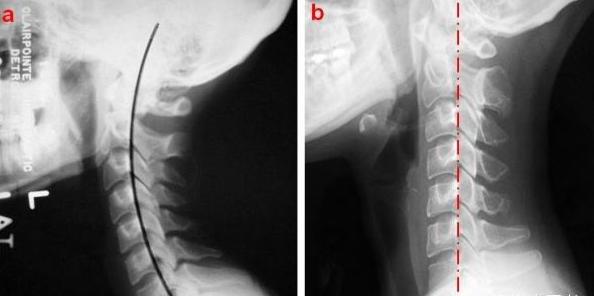

从X光可看到脊椎连线异常:生理曲度改变,椎体滑脱等、脊柱侧弯、棘突偏歪等。以上描述与临床症状的定位诊断不一致。